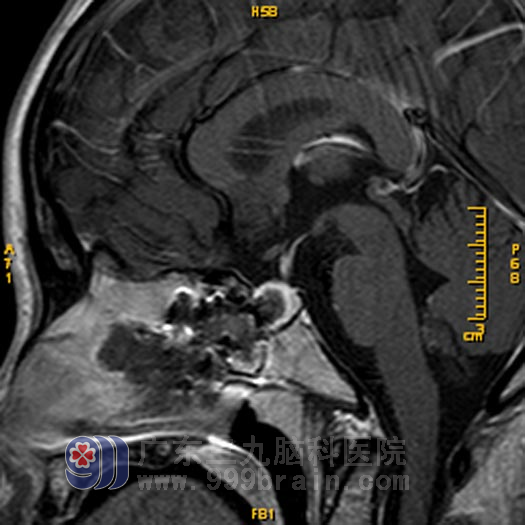

4月1日,珠珠在全麻下行“经鼻蝶鞍区占位切除术”,术中使用导航仪进行肿瘤定位,经过2个多小时,在显微镜下将肿瘤全切。术后经过专科监护,没有出现尿崩等不良并发症。住院一周左右,顺利出院。术后病理回报为:PRL表达型垂体腺瘤。

手术后